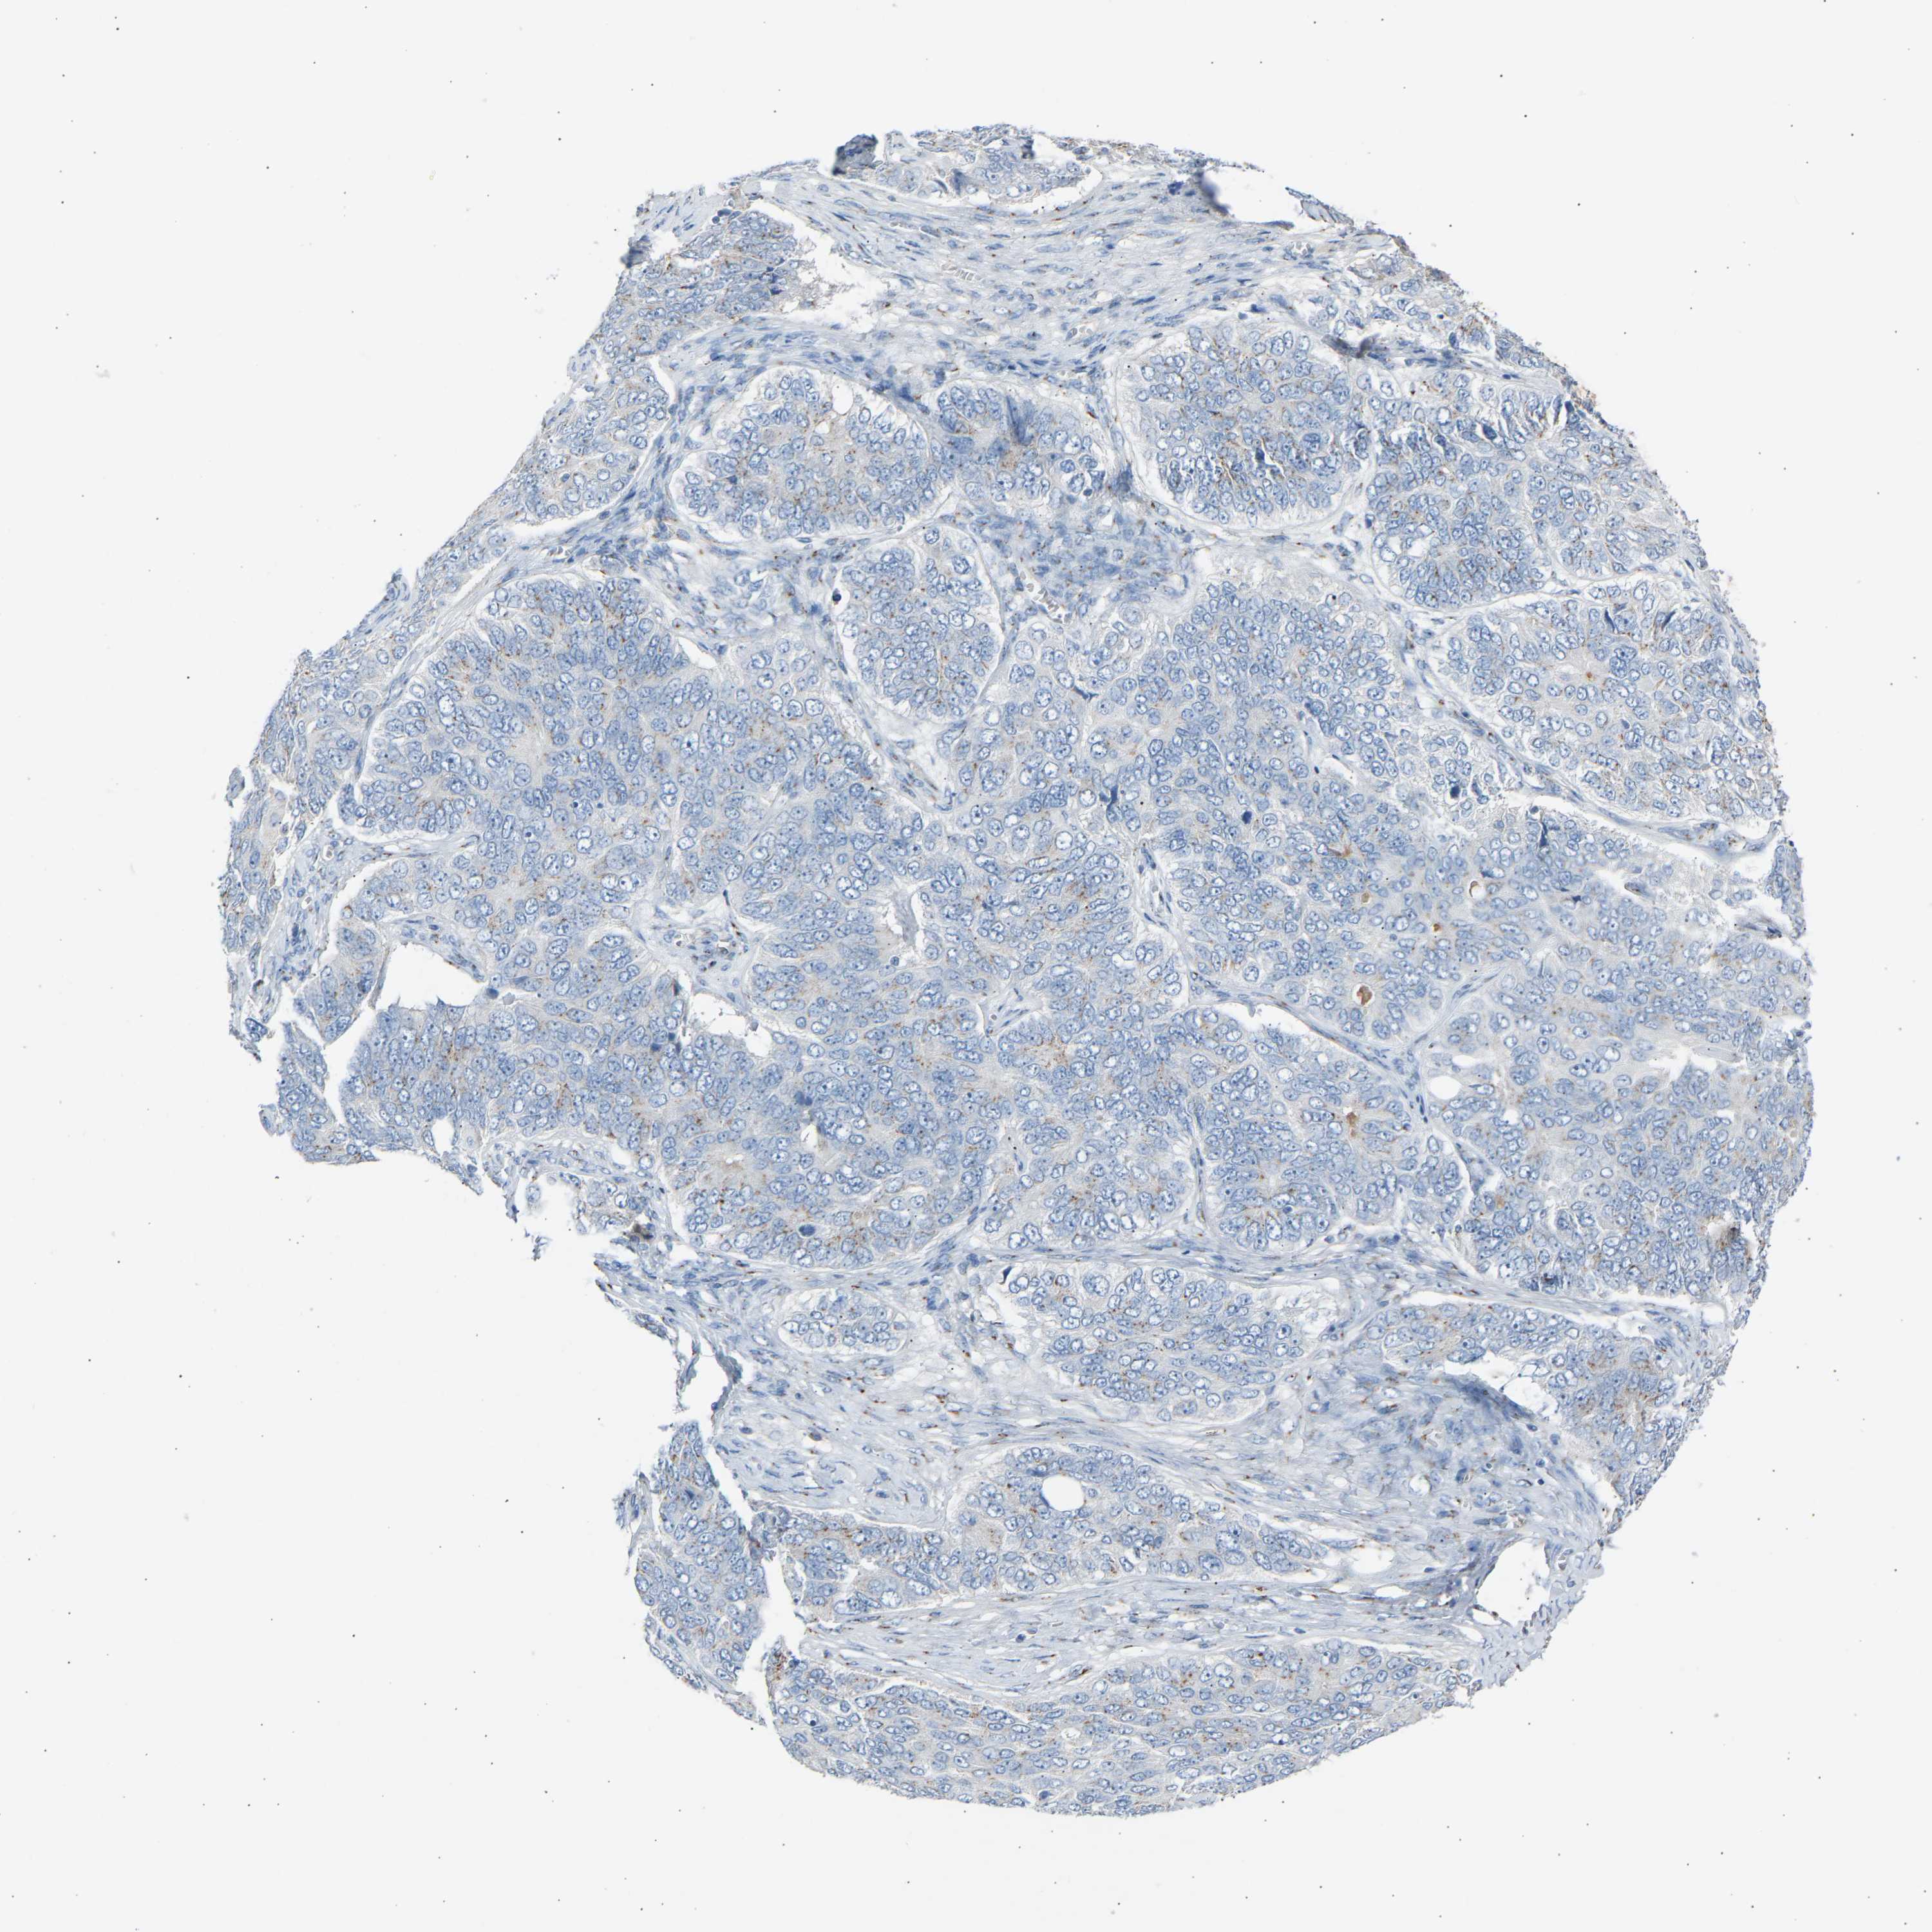

OVARIAN CANCER - Protein expressioni

A mouse-over function shows sample information and annotation data. Click on an image to view it in a full screen mode. Samples can be filtered based on level of antibody staining by selecting one or several of the following categories: high, medium, low and not detected. The assay and annotation is described here.

Note that samples used for immunohistochemistry by the Human Protein Atlas do not correspond to samples in the TCGA dataset.

Antibody stainingi

Antibody staining in the annotated cell types in the current human tissue is reported as not detected, low, medium, or high, based on conventional immunohistochemistry profiling in selected tissues. This score is based on the combination of the staining intensity and fraction of stained cells.

Each image is clickable and will lead to virtual microscopy that enables deeper exploration of all samples and also displays staining intensity scores, fraction scores and subcellular localization as well as patient and tissue information for each sample.

Antibody HPA020060

Cystadenocarcinoma, serous, NOS

Carcinoma, endometroid

Cystadenocarcinoma, mucinous, NOS

Carcinoma, NOS